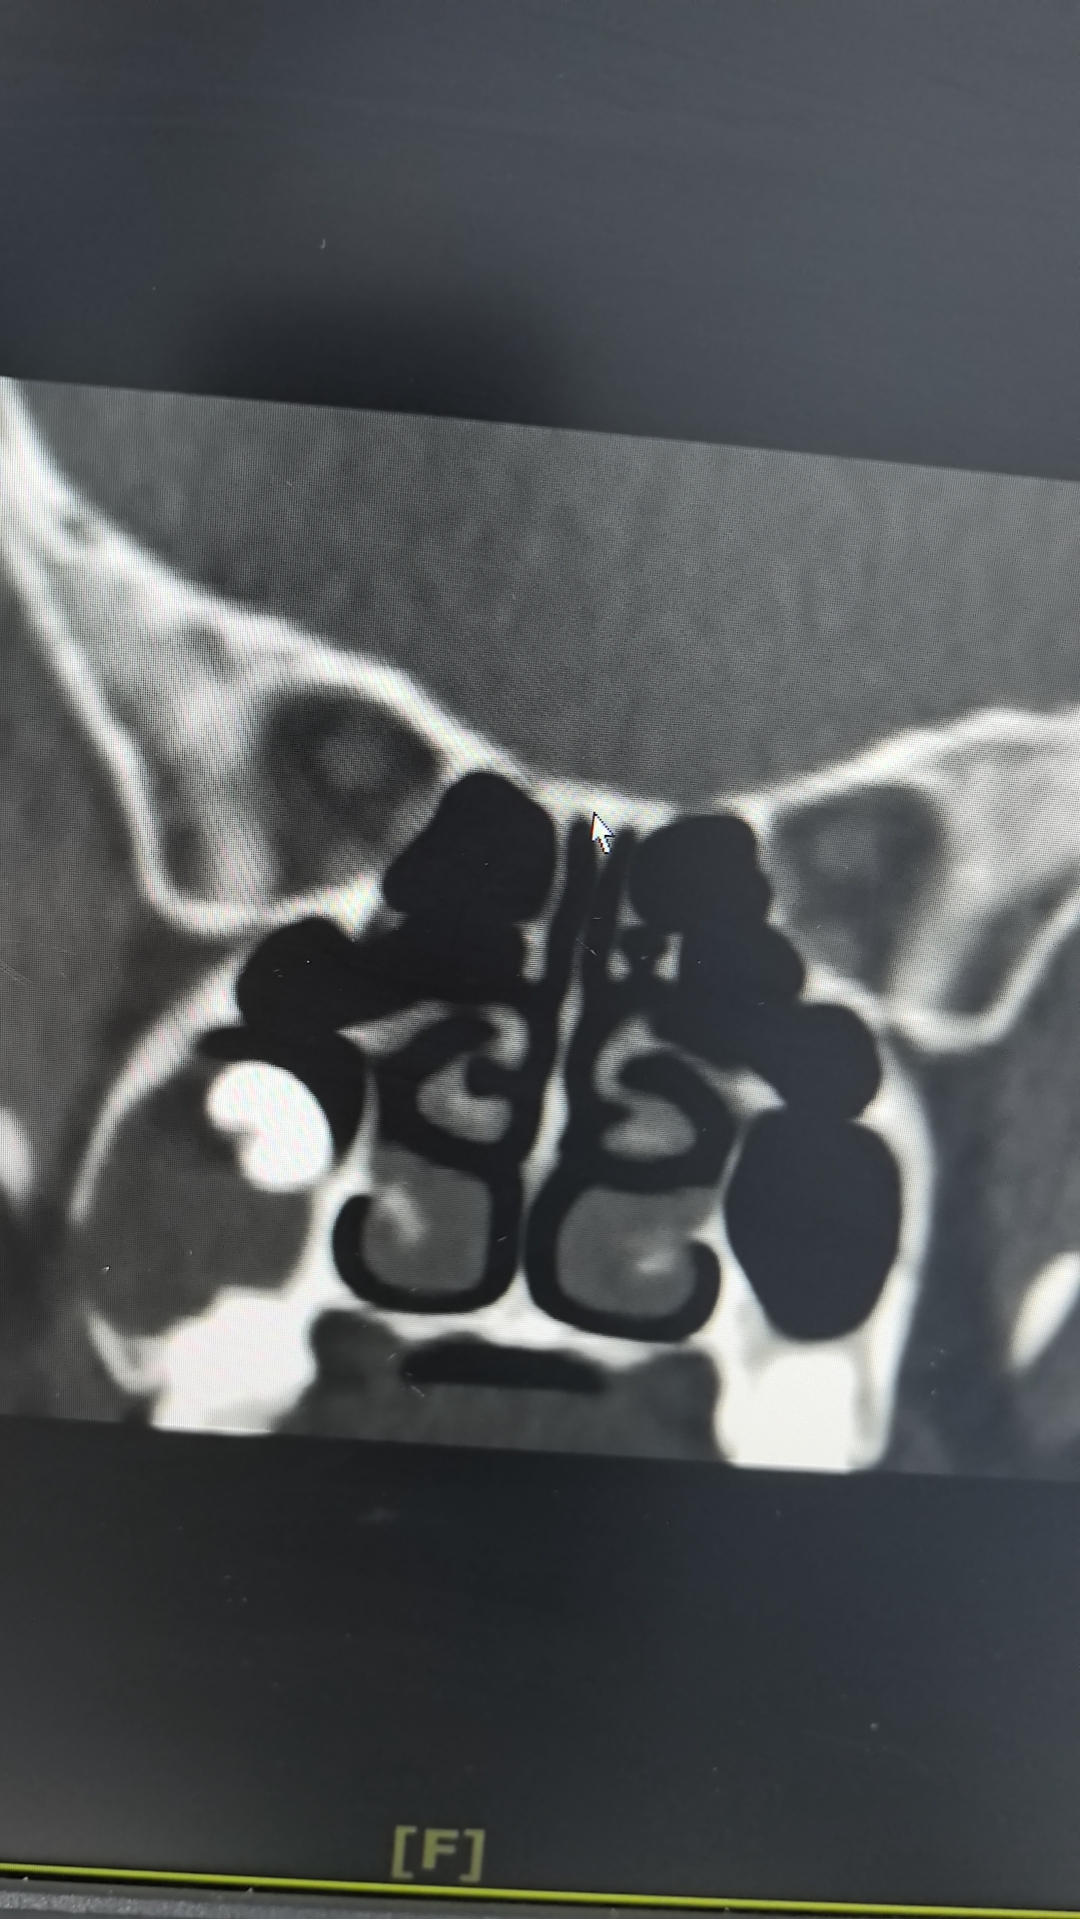

異位牙多見于口腔,但發(fā)生于鼻竇腔內(nèi)者極為罕見。該患者因慢性鼻竇炎就診,術(shù)前CT雖提示竇內(nèi)埋伏牙及周圍囊性灶包裹,但性質(zhì)不明。術(shù)中在鼻內(nèi)鏡下見上頜竇內(nèi)一完整“橢圓形”新生物,憑借豐富的臨床經(jīng)驗(yàn)、解剖知識(shí)和高清內(nèi)鏡的放大視野,手術(shù)團(tuán)隊(duì)精準(zhǔn)分離周圍組織,剝開“卵殼”,其內(nèi)見一完整牙齒,而后將牙齒及其余新生物順利取出。并同期處理了病變鼻竇,最大程度保留了正常黏膜。